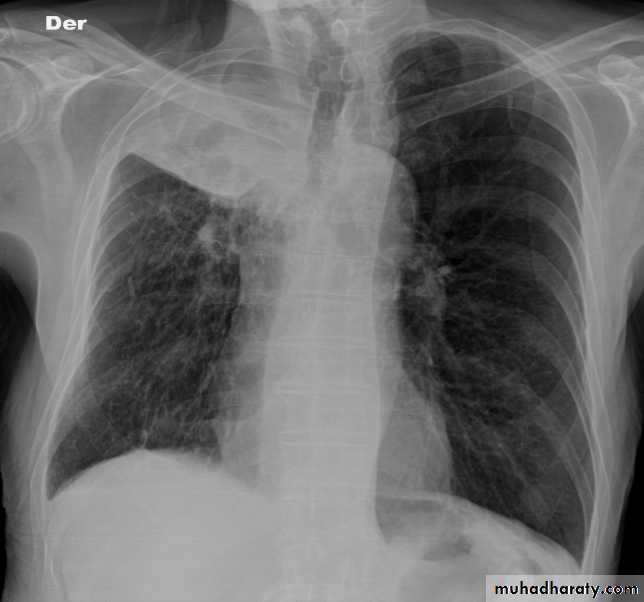

Dextro cardia

21.Dextrocardia .